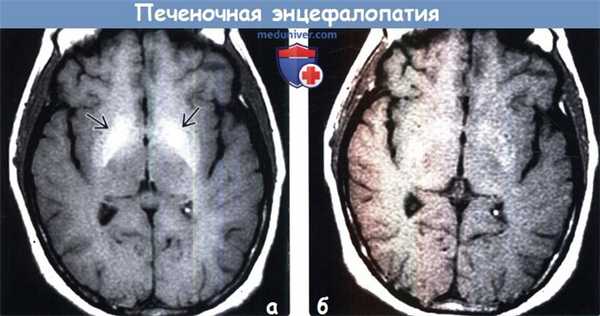

При хронической печеночной недостаточности Т1-режим МРТ часто демонстрирует гиперинтенсивность бледного шара, гипоталамуса и гипофиза. Это связано с отложением марганца, который коррелирует с тяжестью печеночной недостаточности (Pujol et al., 1993; Genovese et al., 2000). Токсичность марганца, обратимая при прекращении поступления марганца при парентеральном питании (Barron et al., 1994), может быть важным фактором в таких случаях.

о ОПЭ: двусторонний отек извилин с повышением интенсивности сигнала от них на T2-BИ/FLAIR (более выражено в области коры островковых долей, поясных извилин) в сочетании с ограничением диффузии

о ХПЭ: двустороннее повышение интенсивности сигнала от базальных ганглиев (БГ) на Т1-ВИ, в частности, от бледных шаров (БШ)

(а) МРТ, FLAIR, аксиальный срез: у пациента с циррозом печени во время эпизода печеночной энцефалопатии определяется симметричное повышение интенсивности сигнала от кортикоспинальных трактов в обоих больших полушариях. При обследовании, проведенном несколькими месяцами позже, (изображения не представлены) наблюдалось восстановление нормальных сигнальных характеристик.

(б) МРТ, Т2-ВИ, корональный срез: у пациента с хронической печеночной энцефалопатией визуализируется характерное снижение интенсивности сигнала от базальных ганглиев.

(а) МРТ, выполненная перед трансплантацией печени, Т1-ВИ, аксиальный срез: определяется симметричное повышение интенсивности сигнала от бледных шаров, что является типичным проявлением хронической печеночной энцефалопатии.

(б) МРТ, Т1 -ВИ, аксиальный срез: у того же пациента через 14 месяцев после трансплантации печени наблюдается практически полное разрешение выявленного ранее повышения интенсивности сигнала. Также произошло разрешение двигательных нарушений у пациента. Как клинические, так и рентгенологические признаки гепатоцеребральной дегенерации имеют потенциально обратимый характер.

• После терапии в первую очередь происходит разрешение клинических проявлений и изменений поданным МР-спектроскопии, через 3-6 месяцев после этого наблюдается нормализация сигнала от БГ

• Аномальные изменения сигнала от БГ обычно нормализуется в течение первого года после трансплантации печени